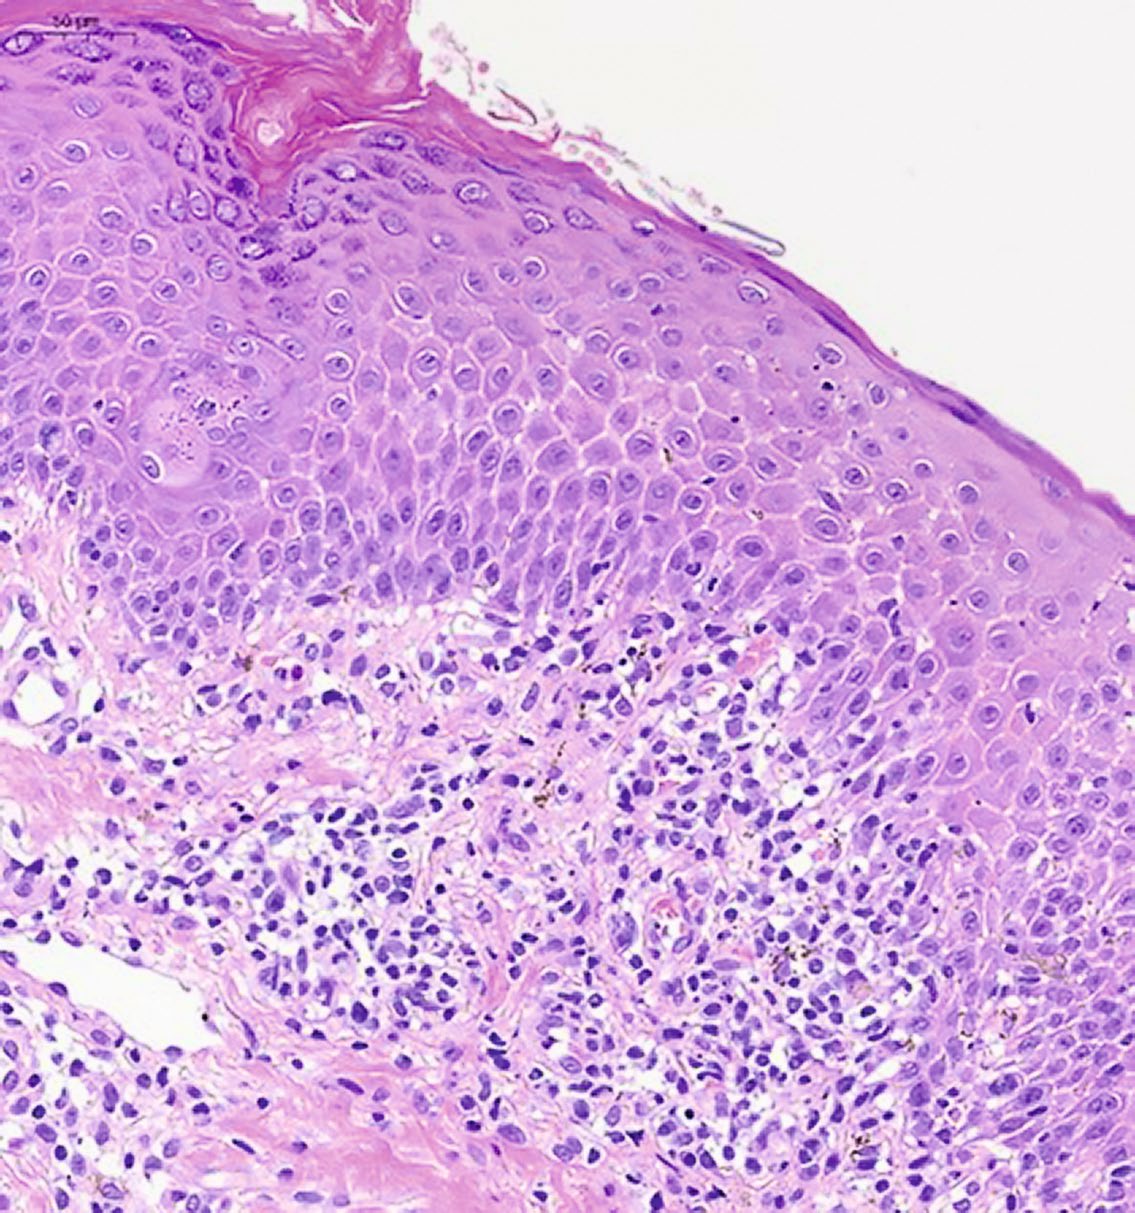

При гистологическом исследовании фрагмента кожи с окраской гематоксилином и эозином выявлен эпидермис с нерегулярным слабо выраженным акантозом, признаками чередования участков пара- и ортокератоза, перифолликулярными участками паракератоза, корками на поверхности, фолликулярными кератиновыми пробками (рис. 2). В верхних слоях дермы обнаруживается периваскулярный лимфогистиоцитарный инфильтрат с участками выраженного эпидермотропизма, в проекции которых эпидермис демонстрирует выраженный спонгиоз (рис. 3), признаки вакуольной дистрофии, содержит многочисленные тельца Сиватта (рис. 4). Среди клеток инфильтрата видны мелкие фрагменты коллагеновых волокон. Кровеносные сосуды сосочкового слоя дермы расширены, придатки кожи сохранены.

Рис. 2. Изменения в эпидермисе — акантоз, чередование участков пара- и ортокератоза, перифолликулярный паракератоз, окраска гематоксилином и эозином, ×100

Рис. 3. Периваскулярный лимфогистиоцитарный инфильтрат дермы, окраска гематоксилином и эозином, ×200

Рис. 4. Тельца Сиватта в эпидермисе, окраска гематоксилином и эозином, ×200